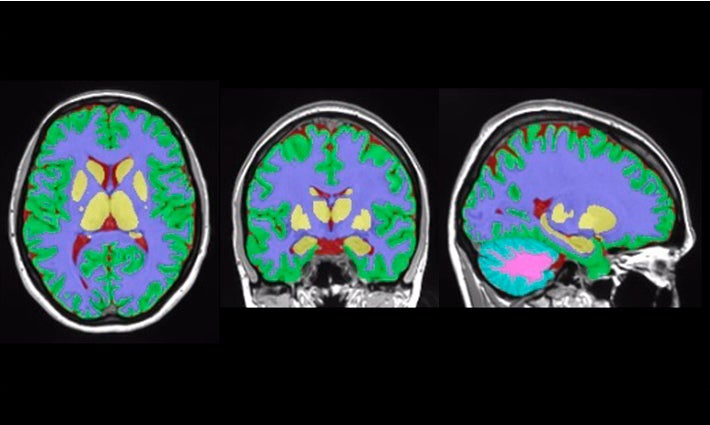

Vol2Brain és capaç d’analitzar fins a 135 regions del cervell, a partir d’imatges de Ressonància Magnètica (RM) del cervell. Ofereix DADES sobre els volums dels teixits de la cavitat intracranial (ICC), així com d’algunes àrees macroscòpiques com els hemisferis cerebrals, el cerebel i el tronc cerebral. A més, proporciona també els volums i índexs d’asimetria d’estructures corticals i subcorticals, de gran importància en l’àmbit neurològic, així com mesures de gruix cortical.

A més, una altra de les característiques «més interessants» del nou sistema és el fet que pot usar-se en subjectes amb lesions en substància blanca, com per exemple pacients amb esclerosi múltiple.

«En la versió anterior del nostre programari, en volBrain, la presència d’aquestes lesions afectava la precisió de les mesures. Amb aquesta nova versió s’estén l’àmbit d’aplicació a un major rang de situacions patològiques», afig Manjón.